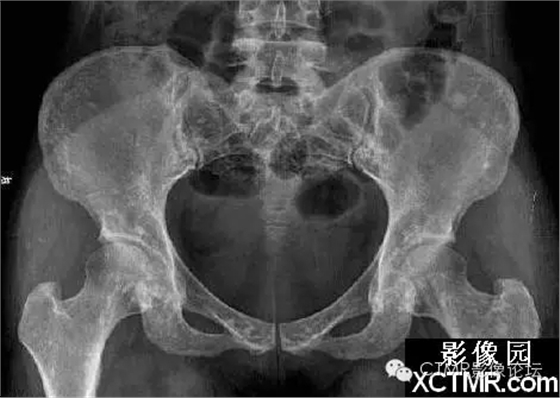

骨斑點(diǎn)癥是一種罕見(jiàn)病,可無(wú)任何臨床癥狀。是由于骨內(nèi)具有彌漫性斑點(diǎn)狀致密骨質(zhì)而得名。既往文獻(xiàn)曾稱局限性骨質(zhì)增生癥、彌漫性濃縮性骨病、家族性彌漫性骨硬化癥、點(diǎn)狀致密骨病等。特點(diǎn)為松質(zhì)骨內(nèi)有彌漫性圓點(diǎn)狀致密影。臨床上可無(wú)任何癥狀,一般為X線檢查所發(fā)現(xiàn)??梢?jiàn)于任何年齡,男多于女。血鈣、磷正常。

骨斑點(diǎn)癥具有以下特點(diǎn):

(1)本病無(wú)臨床癥狀,均為查體或檢查其它病時(shí)發(fā)現(xiàn)本病。

(2)本病與年齡性別無(wú)關(guān),本組從22~58歲,文獻(xiàn)報(bào)道年齡從4個(gè)月~90歲均有發(fā)病。

(3)病灶呈彌漫性多發(fā)的密度增大的圓形、橢圓形、圓圈狀、結(jié)節(jié)狀陰影,其形態(tài)走行,部分與骨的長(zhǎng)軸一致。

(4)病灶多累及長(zhǎng)骨的兩端,密集于干骺端及骨骺,以及骨盆、手、足及不規(guī)則骨。越靠近關(guān)節(jié)病灶越密集,且密度越濃。病灶可相互融合成片而遮蓋正常骨組織。

(5)密度增濃的斑點(diǎn)狀病灶的邊緣不甚清晰銳利,越靠近中心部位密度越濃,邊緣部位密度略淡。

(6)病灶侵及骨的松質(zhì)骨。骨膜及關(guān)節(jié)軟骨不受侵犯,故關(guān)節(jié)間隙光整清晰。

(7)ECT檢查見(jiàn)顯影后骨骼放射性分布不均勻,骨松質(zhì)內(nèi)有多個(gè)大小不等的骨鈣化灶。骨顯像對(duì)應(yīng)性放射性增強(qiáng)。據(jù)上述表現(xiàn)視全身骨顯像多處骨代謝增強(qiáng)灶,為骨質(zhì)代謝異常。

(8)本病應(yīng)與成骨性轉(zhuǎn)移相鑒別。成骨性轉(zhuǎn)移首先應(yīng)有原發(fā)性病灶并轉(zhuǎn)移灶呈單發(fā)或散在多發(fā)性骨質(zhì)增濃病灶,無(wú)密集對(duì)稱性。其病灶直徑均較大,直徑一般在1.0cm以上,同時(shí)伴有明顯的疼痛癥狀。與本病鑒別不難。還應(yīng)與蠟淚樣骨相鑒別。